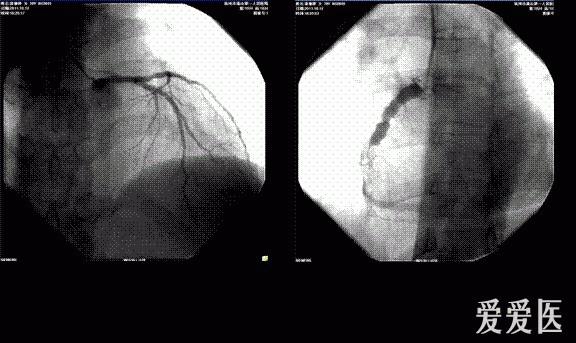

诊疗过程:2011.10.12急诊选择性冠脉造影,结果显示:左冠前降支轻度狭窄,右冠近端、中远段瘤样扩张,内径达10mm左右,右冠中段病变,95%狭窄,狭窄后血栓影,远端血流TIMI2级。将JR46F大腔导管送到右冠开口,送入0.014"runthrough导丝,跨过狭窄处送至右冠远端,然后沿引导钢丝送入抽吸导管到病变处多次抽吸,抽吸血液中可见少量血栓,血栓负荷明显减少,随后送入cordis2.5x15mm球囊,定位于狭窄段,8Kpa扩张球囊1次,重复造影显示残存狭窄85%,但后降支闭塞,0.014"runthrough导丝送入后降支,cordis2.5x15mm球囊8Kpa扩张后血流恢复,改用cordis3.5x15mm球囊定位右冠中段病变处,10kpa扩张后,残存狭窄仍有75%,右冠远端血流TIMI1级,试图进入另一根0.014"runthrough导丝,但在右冠近端瘤样扩张处受阻,结束手术,术中共用肝素针30mg,优维显130ml,期间病人无明显不适,撤出导管,拔除桡动脉鞘管加压包扎,送回病房,嘱右上肢制动,常规抗生素预防感染、心电图、心电监护、注意生命体征及伤口出血血肿和胸痛胸闷等情况。8药物治疗及检查:考虑患者右冠急性血栓形成,予替罗非班应用,同时监测凝血谱、血小板,根据凝血谱、血小板情况调整替罗非班剂量。术后患者血压偏低,一直予多巴胺针微泵维持血压。停用替罗非班针后继续予速碧林针4100iu q12h抗凝,拜阿司匹林片100mg qd、玻立维片75mg qd抗血小板,立普妥片20mg qd调脂,瑞安吉针改善心肌能量代谢,美卓乐片6mg qd治疗系统性红斑狼疮,泮托拉唑针抑酸护胃,阿魏酸哌嗪片、金水宝胶囊改善肾功能,补达秀片补钾。入院来患者一直血压偏低,多巴胺针小剂量维持下血压波动于90/60mmHg,心率70次/分,律齐,心电监护示:窦性心律,未见明显心律失常。2011.10.25停用多巴胺针后血压基本波动予90-100/55-65mmHg左右,患者又有心悸等自觉症状,心电监护可见窦性心律,频发室性早搏,复查心电图示窦性心律下壁、前侧壁、正后壁异常Q波伴ST-T改变。频发室性早搏,部分二联律电轴左偏提示左前分支传导阻滞 左胸导联低电压;急查血电解质K 3.1mmol/l,予静脉+口服加强补钾治疗,第二天复查血钾为4.0mmol/L,但室性早搏仍频发,继续予口服补钾及小剂量倍他乐克12.5mgbid口服后,患者心悸症状缓解不明显。2011.10.16动态心电图:窦性心律伴间歇性窦性心律不齐 房性早搏占<1%,为单发室性早搏占<1%,为单发ST-T改变。2011.10.20查心脏彩色多普勒+左心功能测定+室壁运动分析:(1)左室下壁局部收缩活动稍减弱;(2)主动脉瓣轻度返流;(3)二尖瓣轻度返流;(4)三尖瓣轻度返流;(5)肺动脉瓣轻度返流。(1)主动脉根部内径31舒张期室间隔厚度8左房内径29舒张期左室后壁厚度9左室舒张末期内径52射血分数(EF%)72.9左室收缩末期内径30。(2)左房左室内径正常,左室壁不增厚,静息状态下左室下壁局部收缩活动稍减弱。(3)二尖瓣不增厚,开放不受限,CDFI见轻度返流。二尖瓣血流图示E峰>A峰。(4)主动脉不宽,主动脉瓣不增厚,开放不受限,CDFI:见轻度返流,主动脉瓣瓣口最高流速约1.24m/s。(5)右心正常大,肺动脉内径20mm,CDFI:肺动脉瓣轻度返流,三尖瓣见轻度返流。CW据三尖瓣返流估测肺动脉收缩压23mmHg。2011.10.20心电图:窦性心律 下壁、前侧壁、正后壁异常Q波伴ST-T改变,请结合临床 左胸导联低电压。2011.10.30动态心电图:窦性心律 偶见房性早搏占<1% 室性早搏占15%部分呈三联律 前侧壁异常Q波伴ST-T改变,请结合临床与常规心电图.。

本帖最后由 新郑李永刚 于 2012-1-29 14:57 编辑 系统性红斑狼疮突发急性心肌梗塞救治一例 作者:吴瑰丽彭俊黄建振钱正明 一般情况:患者,女性,39岁 主诉:胸闷8小时入院。 现病史:患者8小时前突发胸闷不适,以胸骨下端憋闷为主,自觉憋闷区域约手掌大小,伴胸骨后压榨感,出冷汗,有恶心及呕吐1次,呕出少许胃内容物,无明显胸痛,无头晕、晕厥,无气急,无头痛等,症状呈持续性,经休息后稍有缓解。约100分钟后患者至我院急诊,急诊心电图提示:窦性心律、急性下壁、正后壁、高侧壁心肌梗死。心肌酶谱、肌钙蛋白:AST 21U/L LDH 270U/L CK 36U/L CK-MB 10U/L cTnI<0.01μg/L”,急诊考虑患者“急性心肌梗塞”,临时予阿司匹林片300mg嚼服、玻立维片300mg顿服等对症处理,并请心内科会诊及取得家属意见予尿激酶150万u溶栓治疗,溶栓2小时后复查心电图提示:窦性心动过缓,急性下壁正后壁心肌梗死。患者仍有胸闷不适,出汗多,心电图ST段下降不明显,考虑溶栓效果欠佳,经与家属沟通,取得知情同意后拟行“冠脉造影”检查及进一步治疗,拟“急性心肌梗死,系统性红斑狼疮”收住入院。病来意识清,精神软,未进食,小便自解,大便未解,体重未见明显增减。 既往史:既往体质偏弱,有“系统性红斑狼疮”病史32年,平时坚持服用美卓乐片。有“高血压病”病史4年,平时坚持服用安博维片,血压控制可。否认有“中风”病史,否认有“冠心病”病史,否认有“结核、肝炎”病史,否认有“肾炎,肾功能不全”等慢性肾脏病史,否认有“甲亢、糖尿病”病史,否认有药物、食物过敏史,否认外伤手术史,否认有输血史,常规预防接种。 家族史:父母均健在,母患“帕金森病”,父患“高血压病”,有一哥哥,体健,否认家族内遗传性、传染性疾病史。 体格检查:T37.5℃,BP 107/63mmHg,SPO2 100%,意识清,精神软,平卧位休息,颈静脉充盈,双肺呼吸音低,未闻及干湿啰音,心音低,心律欠齐,可及早搏,心脏各瓣膜听诊区未闻及明显杂音;腹软,无压痛反跳痛,肝脾肋下未及;双下肢不肿,双巴氏征未引出。 辅助检查:心电图(2011.10.12 14:03)示:窦性心律、急性下壁、正后壁、高侧壁心肌梗死。心肌酶谱肌钙蛋白(2011.10.12 14:17)AST21U/L LDH270U/L CK36U/L CK-MB10U/L cTnI<0.01μg/L。 入院诊断:1、急性下壁心肌梗死,KillipsⅠ级;2、系统性红斑狼疮;3、高血压病2级(极高危组)。 诊疗经过:2011.10.12急诊选择性冠脉造影,结果显示:左冠前降支轻度狭窄,右冠近端、中远段瘤样扩张,内径达10mm左右,右冠中段病变,95%狭窄,狭窄后血栓影,远端血流TIMI2级。将JR46F大腔导管送到右冠开口,送入0.014"runthrough导丝,跨过狭窄处送至右冠远端,然后沿引导钢丝送入抽吸导管到病变处多次抽吸,抽吸血液中可见少量血栓,血栓负荷明显减少,随后送入cordis2.5x15mm球囊,定位于狭窄段,8Kpa扩张球囊1次,重复造影显示残存狭窄85%,但后降支闭塞,0.014"runthrough导丝送入后降支,cordis2.5x15mm球囊8Kpa扩张后血流恢复,改用cordis3.5x15mm球囊定位右冠中段病变处,10kpa扩张后,残存狭窄仍有75%,右冠远端血流TIMI1级,试图进入另一根0.014"runthrough导丝,但在右冠近端瘤样扩张处受阻,结束手术,术[根据相关法规进行屏蔽]用肝素针30mg,优维显130ml,期间病人无明显不适,撤出导管,拔除桡动脉鞘管加压包扎,送回病房,嘱右上肢制动,常规抗生素预防感染、心电图、心电监护、注意生命体征及伤口出血血肿和胸痛胸闷等情况。8药物治疗及检查:考虑患者右冠急性血栓形成,予替罗非班应用,同时监测凝血谱、血小板,根据凝血谱、血小板情况调整替罗非班剂量。术后患者血压偏低,一直予多巴胺针微泵维持血压。停用替罗非班针后继续予速碧林针4100iu q12h抗凝,拜阿司匹林片100mg qd、玻立维片75mg qd抗血小板,立普妥片20mg qd调脂,瑞安吉针改善心肌能量代谢,美卓乐片6mg qd治疗系统性红斑狼疮,泮托拉唑针抑酸护胃,阿魏酸哌嗪片、金水宝胶囊改善肾功能,补达秀片补钾。入院来患者一直血压偏低,多巴胺针小剂量维持下血压波动于90/60mmHg,心律70次/分,律齐,心电监护示:窦性心律,未见明显心律失常。2011.10.25停用多巴胺针后血压基本波动予90-100/55-65mmHg左右,患者又有心悸等自觉症状,心电监护可见窦性心律,频发室性早搏,复查心电图示窦性心律下壁、前侧壁、正后壁异常Q波伴ST-T改变。频发室性早搏,部分二联律电轴左偏提示左前分支传导阻滞 左胸导联低电压;急查血电解质K 3.1mmol/l,予静脉+口服加强补钾治疗,第二天复查血钾为4.0mmol/L,但室性早搏仍频发,继续予口服补钾及小剂量倍他乐克12.5mgbid口服后,患者心悸症状缓解不明显。2011.10.16动态心电图:窦性心律伴间歇性窦性心律不齐 房性早搏占<1%,为单发室性早搏占<1%,为单发ST-T改变。2011.10.20查心脏彩色多普勒+左心功能测定+室壁运动分析:(1)左室下壁局部收缩活动稍减弱;(2)主动脉瓣轻度返流;(3)二尖瓣轻度返流;(4)三尖瓣轻度返流;(5)肺动脉瓣轻度返流。(1)主动脉根部内径31舒张期室间隔厚度8左房内径29舒张期左室后壁厚度9左室舒张末期内径52射血分数(EF%)72.9左室收缩末期内径30。(2)左房左室内径正常,左室壁不增厚,静息状态下左室下壁局部收缩活动稍减弱。(3)二尖瓣不增厚,开放不受限,CDFI见轻度返流。二尖瓣血流图示E峰>A峰。(4)主动脉不宽,主动脉瓣不增厚,开放不受限,CDFI:见轻度返流,主动脉瓣瓣口最高流速约1.24m/s。(5)右心正常大,肺动脉内径20mm,CDFI:肺动脉瓣轻度返流,三尖瓣见轻度返流。CW据三尖瓣返流估测肺动脉收缩压23mmHg。2011.10.20心电图:窦性心律 下壁、前侧壁、正后壁异常Q波伴ST-T改变,请结合临床 左胸导联低电压。2011.10.30动态心电图:窦性心律 偶见房性早搏占<1% 室性早搏占15%部分呈三联律 前侧壁异常Q波伴ST-T改变,请结合临床与常规心电图.。 讨论内容:(1)患者SLE病史多年,此次右冠病变是否与SLE有关?而患者右冠病变重,有瘤样扩张,PTCA治疗效果差,接下来的治疗方案? (2)患者应用多巴胺针时无明显心律失常,但是停用多巴胺针后出现室性心律失常,两者之间是否相关? 以下内容需要积分高于 1000 才可查看*********